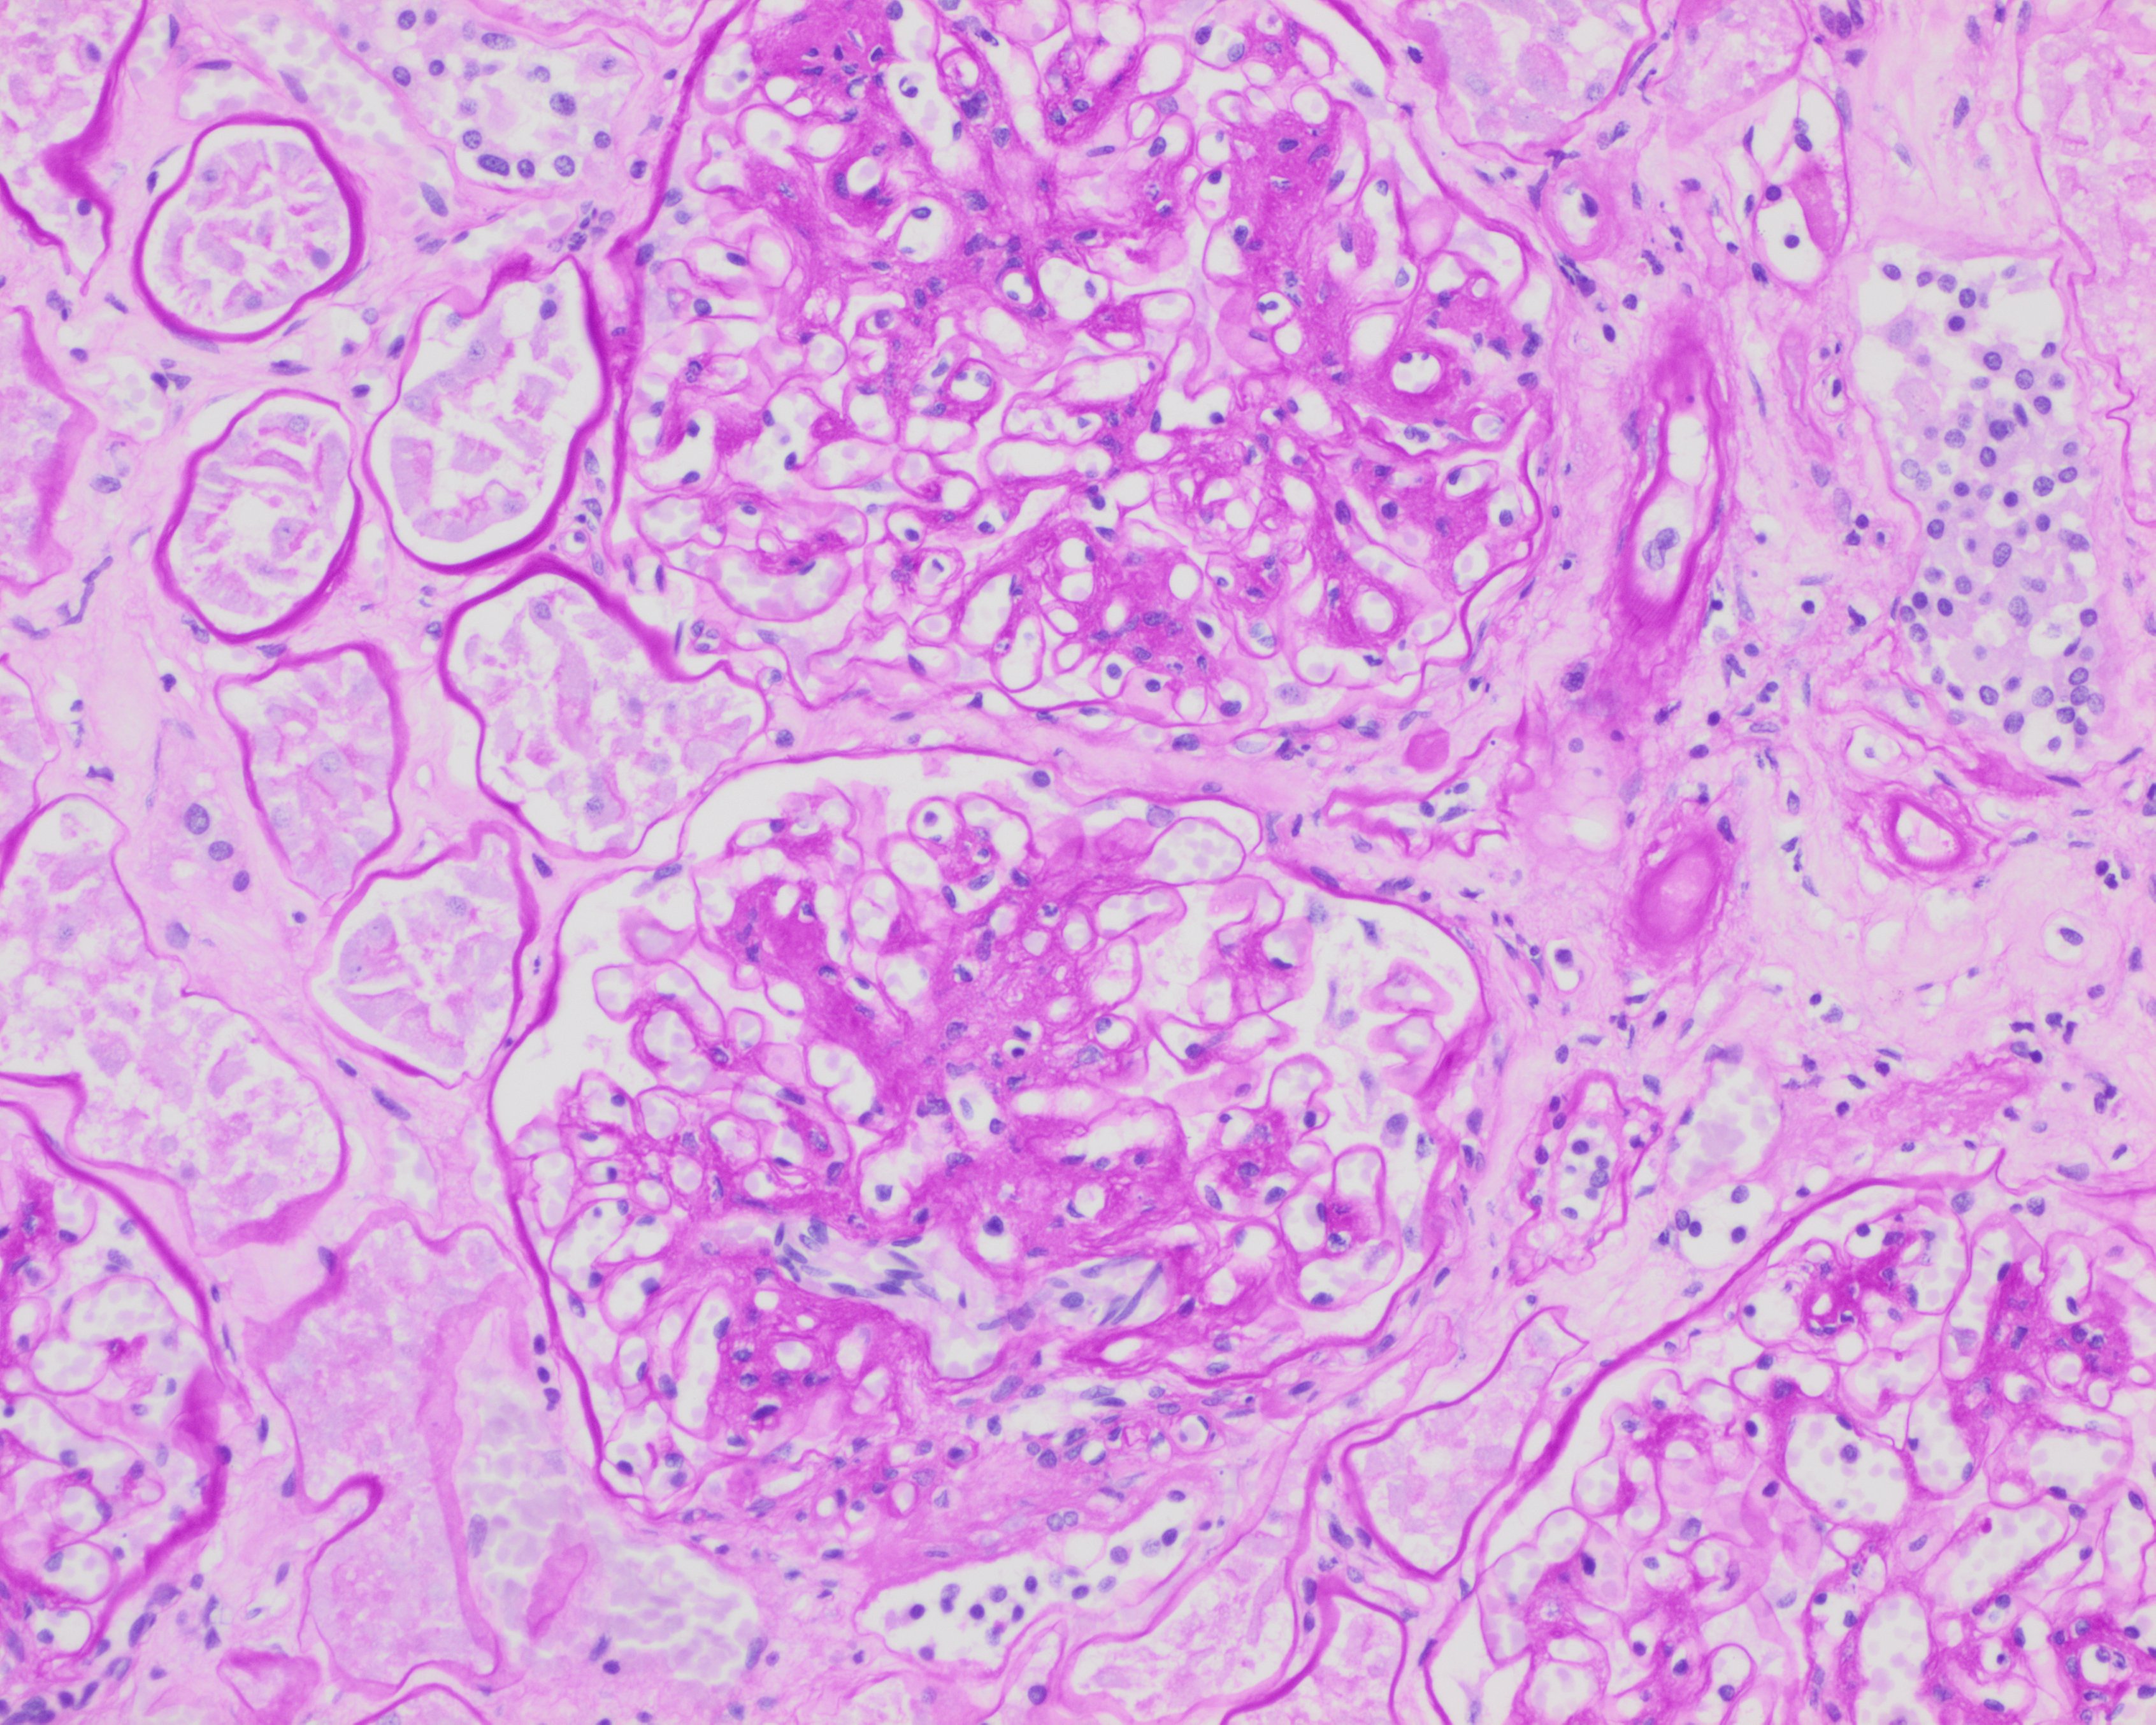

- Kimmelstiel-Wilson nodules and mesangial sclerosis (supported by PAS and/or Jones methenamine silver stains); acellular lesions with a hyaline like core, which may indicate long-standing diabetes. Hypercellular mesangial proliferation may also be seen.

Image: Kimmelstein-Wilson nodule in a glomerulus, PAS staining. (Image credit: Meagan Chambers/University of Washington).

Image: Mesangial expansion in a glomerulus, H&E staining. (Image credit: Meagan Chambers/University of Washington)

Image: Mesangial expansion in glomeruli, PAS staining. (Image credit: Meagan Chambers/University of Washington)

Image: Globally sclerosed glomerulus (top of the image) and a segmentally sclerosed glomerulus (middle of the image) and a non-sclerosed glomerulus with mesangial expansion (bottom of the image) all present in one high power field in a patient with DM on H&E. (Image credit: Meagan Chambers/University of Washington).